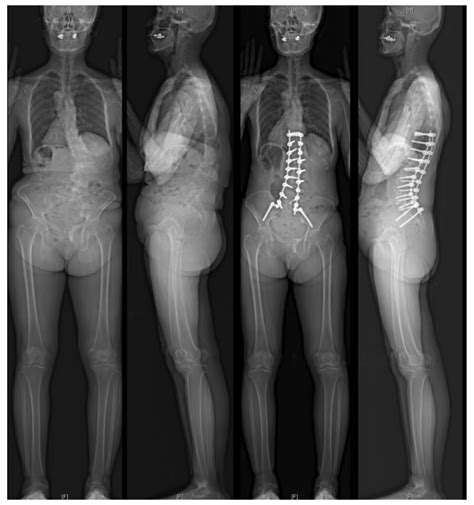

• Surgical Procedures: Surgeons use these terms to plan and execute procedures. Understanding the anterior and posterior positions of organs and tissues is crucial for minimizing risks and ensuring successful outcomes.

• Diagnostic Imaging: Radiologists and other medical professionals use these terms to interpret images from X-rays, MRIs, and CT scans. Accurate identification of anterior and posterior structures aids in diagnosing conditions and planning treatments.